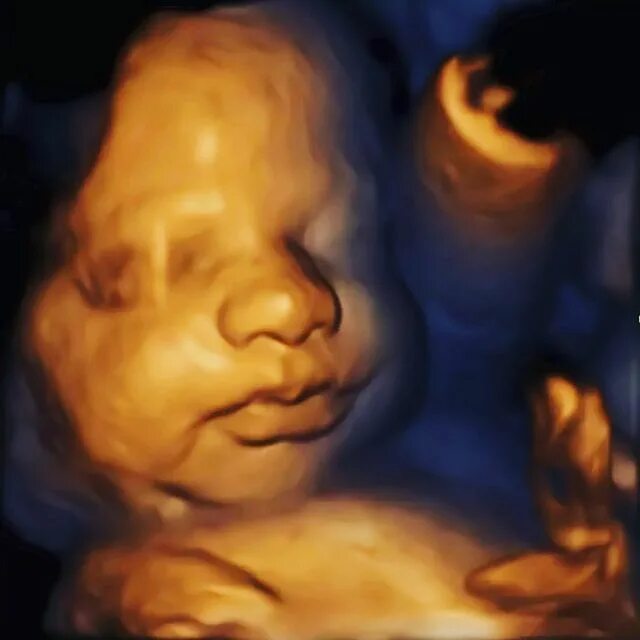

На каком сроке делать 3д